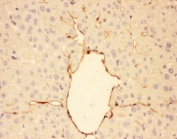

IHC-P testing of rat lung tissue. HIER: steamed with pH6 citrate buffer.